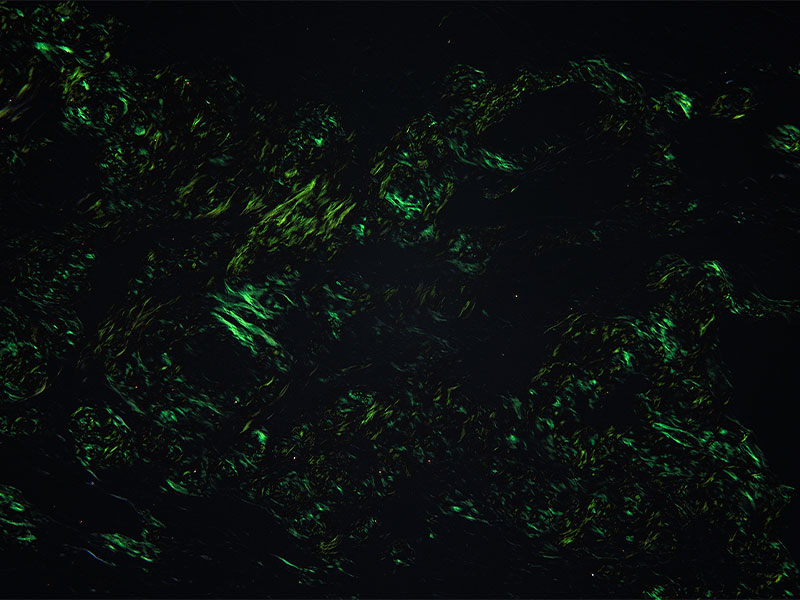

![]() | 640万画素による高解像と忠実な色再現DP23は使いやすさと高い解像度、忠実な色再現性を兼ね備えた顕微鏡用デジタルカメラです。ライフサイエンスや病理研究をはじめ幅広い分野において幅広くお使いいただけます。 |

| 高い色再現性により観察の質を向上自然で忠実な色再現を実現し、目視観察と同等の色味の画像が取得可能です。高演色LED光源を搭載したシステム生物顕微鏡BX53/BX43とUPLXAPOシリーズ対物レンズと組み合わせてお使い頂くことで、色再現性を最大限に発揮します。 |